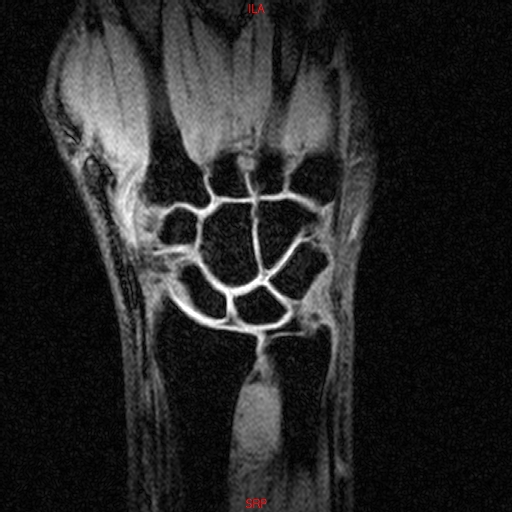

• RESONANCIA NORMAL MUÑECA COR T1 3D FATSAT